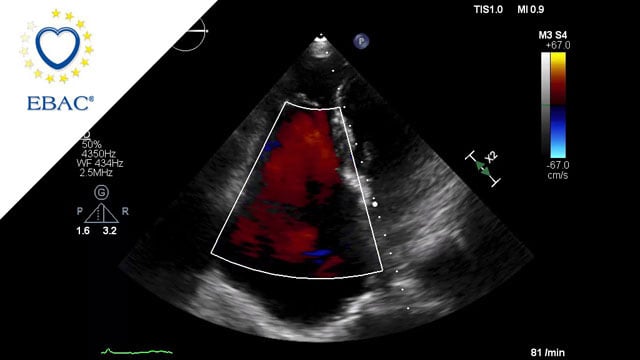

How should I treat a torrential tricuspid valve regurgitation in a young patient who remains symptomatic despite optimal medical therapy?

How should I treat a torrential TR in a young patient who remains symptomatic despite OMT?

A frail patient presents with worsening NYHA class III dyspnoea and peripheral oedema despite optimal medical therapy...